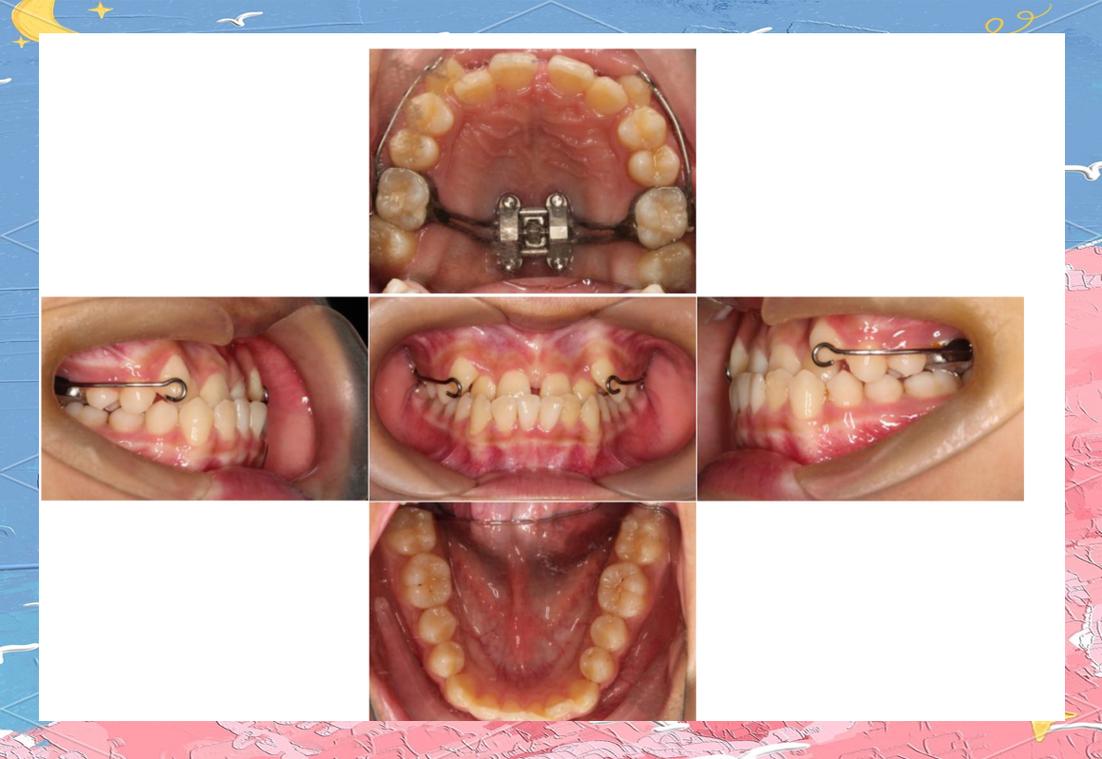

横腭杆(Transpalatal Bar,TPA)和下颌舌弓(Lingual Arch)是传统口内支抗装置,TPA通过焊接于上颌第一磨牙带环的连接杆,将两侧磨牙连成整体,限制其近中倾斜或前移,为前牙内收提供支抗,弱支抗状态下,可选用直径较细(如1.0mm)的不锈钢丝制作TPA,增加其弹性,允许磨牙轻微移动(约1-2mm),同时通过腭部软组织辅助分散力,下颌舌弓原理类似,适用于下颌磨牙支抗不足的病例,通过舌侧基托抵住前牙舌侧,防止前牙唇倾,后牙可少量前移。

Nance弓:利用腭部软组织增强支抗

Nance弓是在TPA基础上增加腭部塑料基托,利用腭穹隆黏膜与骨组织的吸附作用增强支抗,其弱支抗应用体现在:通过调整基托面积(减小基托范围)或选用弹性弓丝(如β钛丝),允许磨牙少量近中移动,同时前牙内收时,基托将部分力传递至腭部,减少后牙支抗损耗,适用于上颌前牙前突、需要少量磨牙前移的病例。